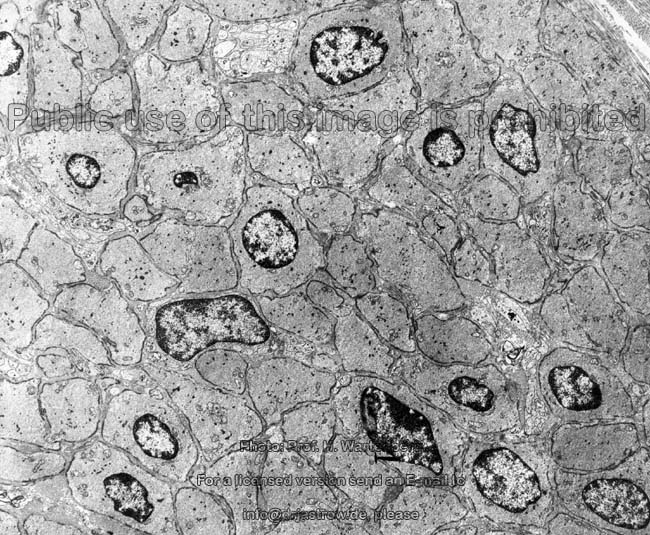

glatte Muskulatur

quer Übersicht (Affe)

quer Detail (Affe)